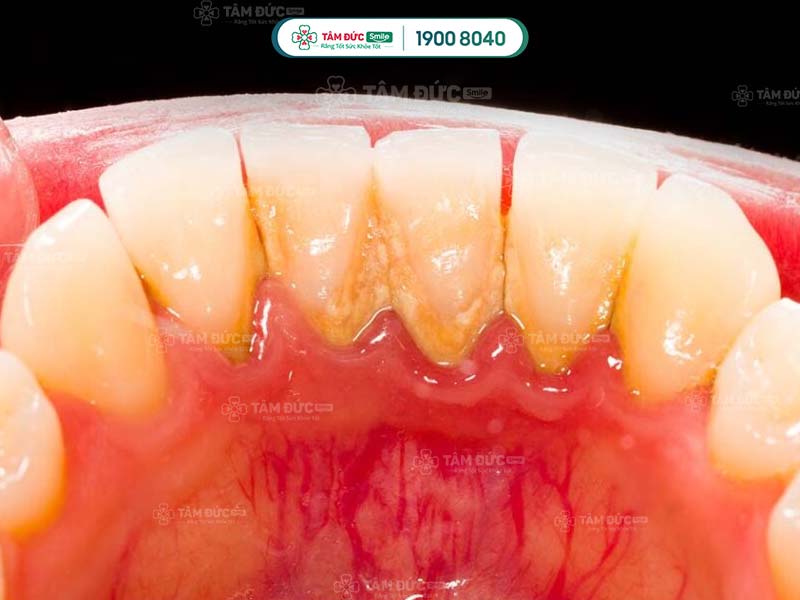

Cao răng cần được làm sạch triệt để bằng các dụng cụ chuyên dụng. Trong xuyên suốt quy trình cạo cao răng, Quý khách có thể bị ê buốt nhẹ.

Nếu cao răng nằm sâu trong chân răng, thao tác cạo cao răng có thể gây chảy máu. Vì vậy, Quý khách cần nhờ đến sự hỗ trợ của bác sĩ giỏi tay nghề để giảm thiểu rủi ro này.